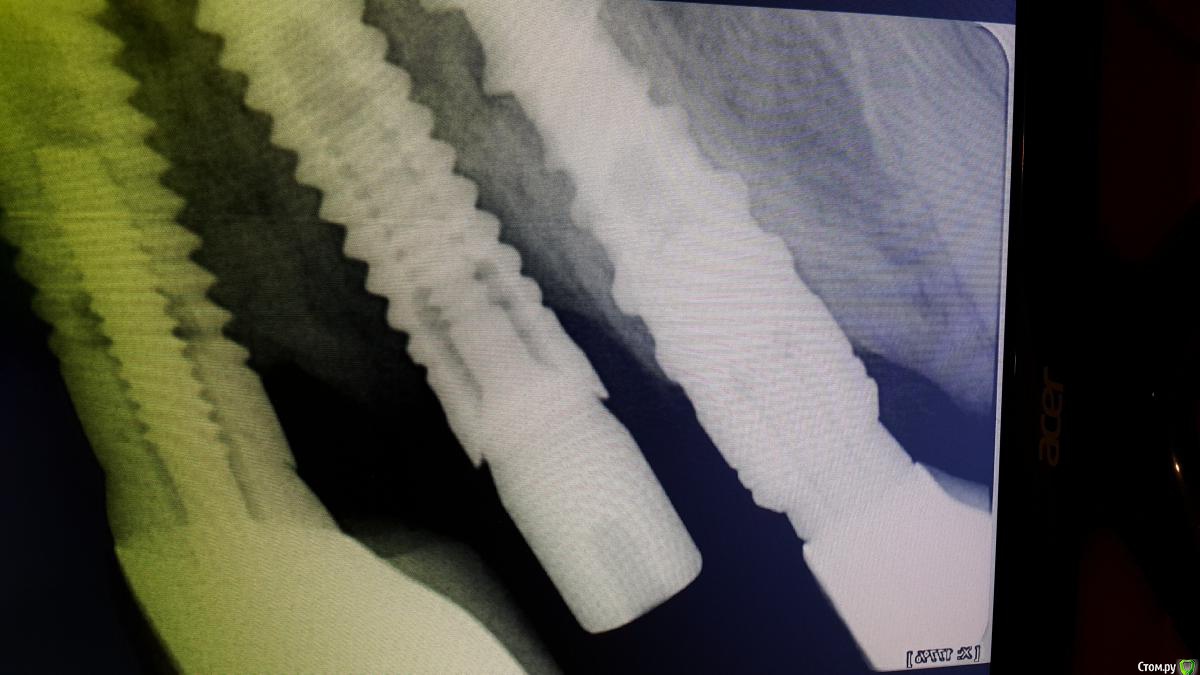

art700 Опубликовано 19 марта, 2015 Автор Поделиться Опубликовано 19 марта, 2015 И сразу второй случай. Ставил пациент имплант не у нас. Протезировать я отказался, хотя опять имплантолог утверждает что все отлично. Консультировался со вторым в другой клинике, предложил выкручивать, затем все по новой. Ссылка на комментарий

red_butler Опубликовано 19 марта, 2015 Поделиться Опубликовано 19 марта, 2015 В первом случае все нормально. Во втором средний винт явно лишний, убрать и протезировать на то что останется 4 Ссылка на комментарий

DentArt Опубликовано 19 марта, 2015 Поделиться Опубликовано 19 марта, 2015 Согласен что во втором случае оставлять средний винт нельзя, убрать и заполнить костным,,, В первом варианте оголение имплантата на несколько витков не критично, но небольшая пластика не помешает,, Ссылка на комментарий

колесников Опубликовано 19 марта, 2015 Поделиться Опубликовано 19 марта, 2015 (изменено) Вопрос не к имплантологу ,а Скорее к ортопеду,в первом случае. Убыль с одной стороны-имеется рычаг,неравномерное распределение нагрузки,при том что параллельность сохранена. Во втором варианте-да лучше средний винт не нагружать. Можно и не убирать,просто заглушить,но пластика слизистой будет не лишней. Изменено 19 марта, 2015 пользователем колесников 1 Ссылка на комментарий